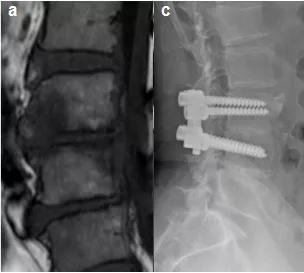

脊柱感染可以通过经皮内镜进行清创引流。

简单来说就是在脊柱上开几个小口,将一个镜子和所需要的器械通过切口伸到脊椎里,将感染坏死的部位切除,并清除脓液。

在病灶清除的同时,可以放置一根管子冲洗引流,具有操作简单、安全性高、创伤小等优势。手术切口一般只有7-9mm大小,可以在局麻下完成,而且出血很少。

此外,如果脊柱病变比较大的话,需要清理的范围也会比较大,脊柱可能会因此失去稳定性。这时候,也可以利用微创技术进行脊柱的固定。

经皮脊柱椎弓根钉内固定术即日常老百姓口中所说的“微创手术”。也是在内镜的帮助下,将钉子放在两个椎体之间,将它们连接固定。它与传统的开放手术相比,有一些突出的优势:

(1)几个1cm的小孔就能完成手术,不用切开过多的肌肉、韧带等组织,从而避免因手术导致的迟发性脊柱不稳。